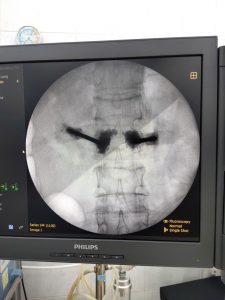

Thông tin thêm về kỹ thuật can thiệp này, BSCKII Đàm Quang Thịnh cho biết: Phẫu thuật tạo hình thân đốt sống bằng xi măng sinh học là một phẫu thuật ít xâm lấn. Xi măng sinh học được bơm vào thân đốt sống với mục đích giảm đau, nâng chiều cao thân đốt sống, tái khôi phục đường cong sinh lý và tăng độ vững cho cột sống. Tại Bệnh viện Bắc Thăng Long phẫu thuật tạo hình thân đốt sống bằng xi măng sinh học được thực hiện hằng ngày, một cách thường quy dưới sự hỗ trợ của hệ thống máy móc hiện đại nên hình ảnh rõ nét giúp phẫu thuật viên thao tác dễ dàng, chính xác, hạn chế tai biến, biến chứng có thể xảy ra cho người bệnh.